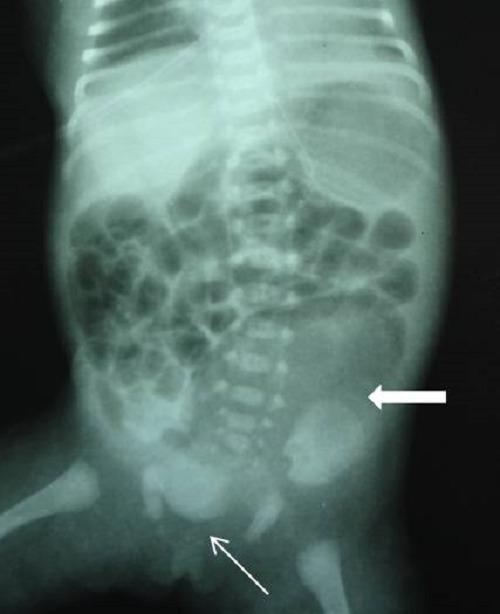

This report describes two newborn girls with single perineal opening (cloaca), and pseudoexstrophy in the form of divergent pubic bones and rectus muscles, and a low-set umbilicus. Both patients had a type II congenital pouch colon (CPC) with one hemiuterus and vagina on each side in the pelvis. In one patient, a Meckel's diverticulum was present 5 cm from the ileocecal junction. In both girls, a diverting proximal ileostomy was the initial surgery.

本报告描述了两名患有单一会阴开口(泄殖腔)的新生女婴,伴有耻骨和腹直肌分离形式的假性膀胱外翻以及低位脐。两名患者均患有II型先天性袋状结肠(CPC),盆腔两侧各有一个半子宫和阴道。其中一名患者在距回盲部交界处5厘米处存在梅克尔憩室。两名女孩最初的手术均为近端回肠转流造口术。